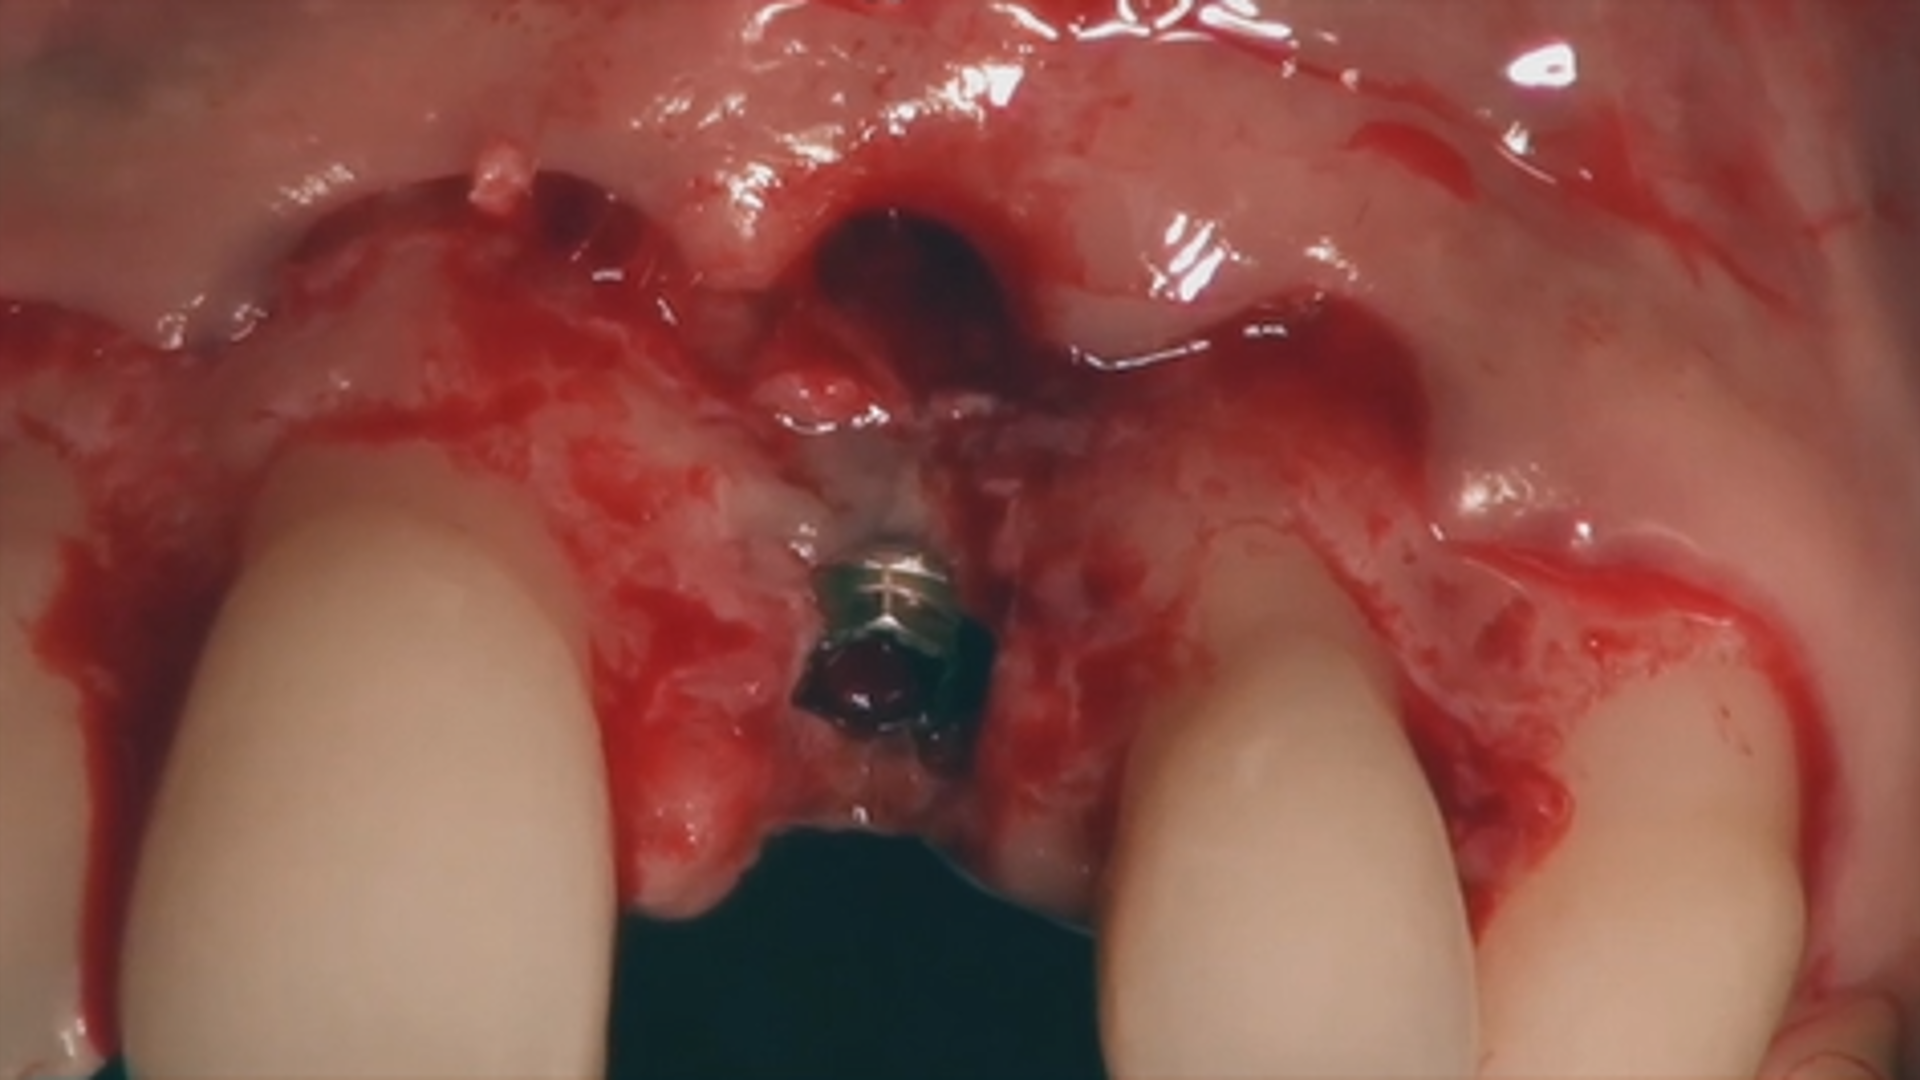

Entire surgical procedure: Coronally Advanced Flap and Connective Tissue Graft

Treatment of soft tissue dehiscence around implants

Mucogingival approach to immediate implant placement (Part 1)

Mucogingival approach to immediate implant placement (Part 2)

Mucogingival approach to immediate implant placement in problematic clinical cases